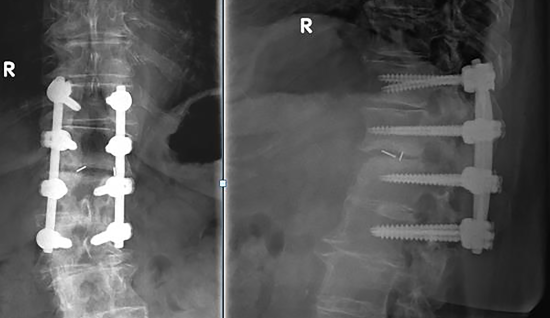

Standing X-ray postoperatively with excellent implant position of T11-L2 with interbody spondylodesis T12/L1